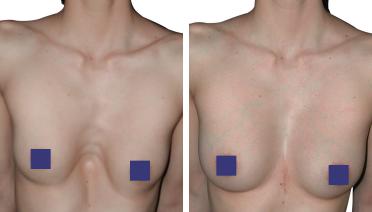

La tecnica di impianto su misura è una tecnica chirurgica minore che consiste nel riempire la concavità creata dal Pectus con un impianto personalizzato. Si tratta di un intervento rapido, a basso rischio, con un risultato immediato e una breve convalescenza.

In questa pagina, troverà i risultati di questa operazione a seconda del tipo di Pectus : mediale, asimmetrico, più o meno profondo o lungo.

Tipo 1 : Mediano, profondo e simmetrico,